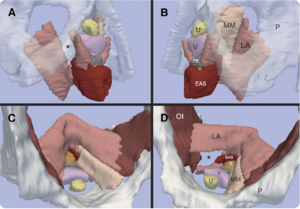

- 4.39 Using Stress MRI to Analyze the 3D Changes in Apical Ligament Geometry from Rest to Maximal Valsalva: A Pilot Study